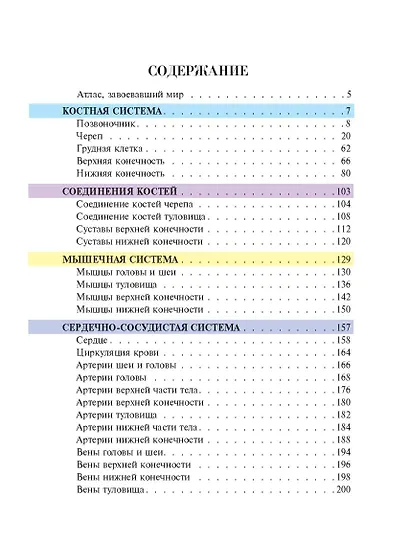

«Популярный атлас анатомии человека» — это оптимальный объем базовых знаний о строении человеческого тела. Созданная современными учеными-анатомами с использованием новейших данных, книга предлагает четко структурированную информацию, изложенную в 10 тематических главах по основным анатомическим системам.

Особую ценность изданию придают высококачественные репродукции классических гравюр из знаменитой «Gray's Anatomy» — самого известного англоязычного учебника по анатомии человека. Более 200 классических иллюстраций выполнены с безупречной детализацией благодаря современным полиграфическим технологиям. Винтажные гравюры XIX века сочетаются с удобным компактным форматом и ярким дизайном, что делает книгу одновременно эстетически привлекательной и практичной в использовании.

"Популярный атлас анатомии человека" — это доступное, красочное и информативное издание, содержащее основные сведения о строении человеческого тела. Написанный ведущими учёными-анатомами с учётом последних научных данных, атлас предлагает систематизированную информацию, разделённую на 10 глав по ключевым анатомическим системам. Книга сочетает в себе ясность изложения и высокое качество визуального материала: она проиллюстрирована классическими гравюрами из знаменитой "Анатомии Грея", что делает изучение анатомии наглядным и увлекательным. Удобный компактный формат практичен в использовании,а цветная печать изображений обеспечивает комфортное чтение и детальное рассмотрение иллюстраций из всемирно известного медицинского учебника.